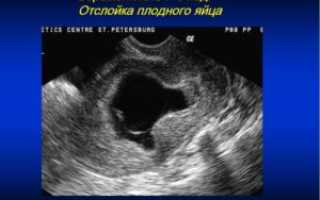

Также плодное яйцо выступает 1-й структурой, различаемой на ультразвуковом исследовании и помогающей подтвердить наличие беременности. Обладает формой овала или круга, увеличивается в размерах с течением времени.

Исходя из диаметра плодного яйца, представляется возможной установка точного термина беременности, а также ее возможных нарушений (доктор оценивает форму и благодаря полученным сведениям выявляет состояние маточного тонуса).

Вместе с отслоением хориона начинают разрываться сосуды, за счет которых он внедрился в матку, в этой области образуется гематома. Именно это и будет самым первым симптомом отслоения, которое обнаруживается на ультразвуковой диагностике. В случае частичной или не сильно выраженной отслойки, гематома может быть единственным проявлением данного патологического состояния.

УЗИ-исследование – это основной способ диагностики этой патологии наряду с общим осмотром врача гинеколога. С помощью ультразвука доктор сможет увидеть наружную оболочку плодного яйца и оценить, в каком она состоянии. Также для него будет важным наличие гематомы между плодным яйцом и хорионом, то есть его оболочкой.

Состояние плода также необходимо оценить. С шестой недели возможно прослушать его сердцебиение. А само плодное яйцо на УЗИ можно обнаружить уже к концу первого месяца беременности.